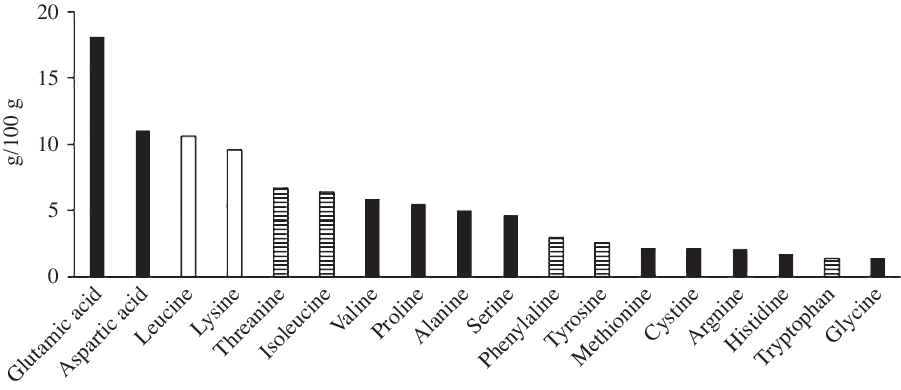

Experimental solutions were prepared by researchers and provided to participants the night before the trial. The protein solution contained 75 g whey protein powder (Myprotein), resulting in an intake of 63 g protein (21 g protein per 25 g serving), 300 ml of water and 0 kJ vanilla flavouring drops to taste (Myprotein). An amino acid profile for the whey protein used is depicted in Fig. 2. The control solution was 300 ml water. Breakfast consisted of 29 % porridge oats (Sainsbury’s), 67 % whole milk (3·7/100 g fat; Sainsbury’s) and 4 % granulated sugar (Sainsbury’s). Porridge was provided in quantities to deliver 1 g CHO/kg body mass, obtained from 80 % oats and 20 % sugar. This resulted in an energy intake of 2356 (sd 435) kJ, containing 18·0 (sd 3·3) g protein and 72·4 (sd 13·9) g CHO. The quantity was replicated for the second trial, regardless of any minor change in body mass. Participants were instructed to consume the porridge within 15 min to standardise effects of eating rate upon appetite hormones(Reference Kokkinos, le Roux and Alexiadou33).

Fig. 2. Amino acid profile of the whey protein used. ![]() , Glucogenic;

, Glucogenic; ![]() , mixed;

, mixed; ![]() , ketogenic.

, ketogenic.

Protein ingestion in excess of physiological needs can stimulate ureagenesis and the use of glucogenic amino acids in gluconeogenesis(Reference Schutz40). Boden & Tappy(Reference Boden and Tappy41) demonstrated the hyperaminoacidaemia following protein ingestion stimulated endogenous glucose production despite hyperinsulinaemia. Studies employing stable isotope methodologies have demonstrated approximately 17–19 % of protein ingested is converted to glucose(Reference Fromentin, Tomé and Nau42,Reference Khan, Gannon and Nuttall43) . Therefore, assuming similar rates in the present study, it could be hypothesised that 17–19 % of the 63 g protein ingested in the present study resulted in glucose production, producing 10·7–12·0 g glucose. This is supported by the findings of Ang et al. (Reference Ang, Bruce and Kowalski44), who demonstrated that a 75 g of whey protein dose resulted in 11 g endogenous glucose production. Fromentin et al. (Reference Fromentin, Tomé and Nau42) state that the percentage of dietary amino acids converted to glucose was mainly related to the provision of glucogenic amino acids. The whey protein utilised in the present study comprised 79·8/100 g glucogenic or mixed amino acids (Fig. 2), providing a high availability of gluconeogenic precursors. In addition, the relative lack of other sources of gluconeogenic precursors (glycerol, pyruvate and lactate) in our whey protein solution, comparative to egg(Reference Fromentin, Tomé and Nau42) or cottage cheese(Reference Khan, Gannon and Nuttall43), may have further increased the contribution of amino acids to gluconeogenesis. Hence, glucose production may have been at the higher end of this estimate.

The time of feeding in the present study may also have impacted gluconeogenesis and insulin sensitivity. Protein was fed at a time when the relative concentrations of both glucagon and cortisol were increasing. Elevated glucagon concentration stimulates hepatic gluconeogenesis and amino acid uptake(Reference Bodo and Altszuler50,Reference Frayn51) , while cortisol also stimulates hepatic gluconeogenesis, alongside reducing insulin sensitivity(Reference Bodo and Altszuler50). Betts et al. (Reference Betts, Beelen and Stokes52) demonstrated that the overnight cortisol response is elevated following the co-ingestion of protein with CHO before bed. Thus, the protein ingestion in the present study may have augmented the natural circadian elevation in cortisol thus reducing insulin sensitivity. There is also evidence for circadian rhythmicity in circulating amino acids, with lowest concentrations between 04.00 and 08.00 hours(Reference Feigin, Klainer and Beisel53,Reference Feigin, Klainer and Beisel54) . Feigin et al. (Reference Feigin, Klainer and Beisel54) demonstrated that the ingestion of a large protein bolus at 08.00 hours resulted in an additional increase in blood amino acid concentrations, exceeding that anticipated from typical circadian periodicity, an interference not replicated with an identical protein load consumed at 20.00 hours. This further supports the idea that the body may not be entrained to deal with a large bolus protein dose at the time of feeding in the present study. Finally, whey protein ingestion and an increase in plasma branched-chain amino acids, particularly leucine, have also been demonstrated to impair insulin sensitivity directly, especially in high doses(Reference Smith, Yoshino and Stromsdorfer55–Reference Flakoll, Wentzel and Rice57). The high branched-chain amino acid (22·6/100 g) and specifically leucine content (10·6/100 g) of the whey protein (Fig. 2) may therefore have impaired glucose uptake via that mechanism. As such, any priming effect of insulin secretion following protein ingestion may have been insufficient to overcome this reduced insulin sensitivity at breakfast. Therefore, the arrival of a large dose of amino acids at an atypical time of day might, via the hypothesised influence on hepatic gluconeogenesis and insulin sensitivity, result in impaired glucose control upon waking in a manner specific to this time frame. This further highlights the novel nature of the present study employing an atypical feeding time. Additional study is warranted to investigate if the glucose tolerance to a second meal is impaired following protein ingestion prior to other daily meals in a more ‘conventional’ feeding pattern.